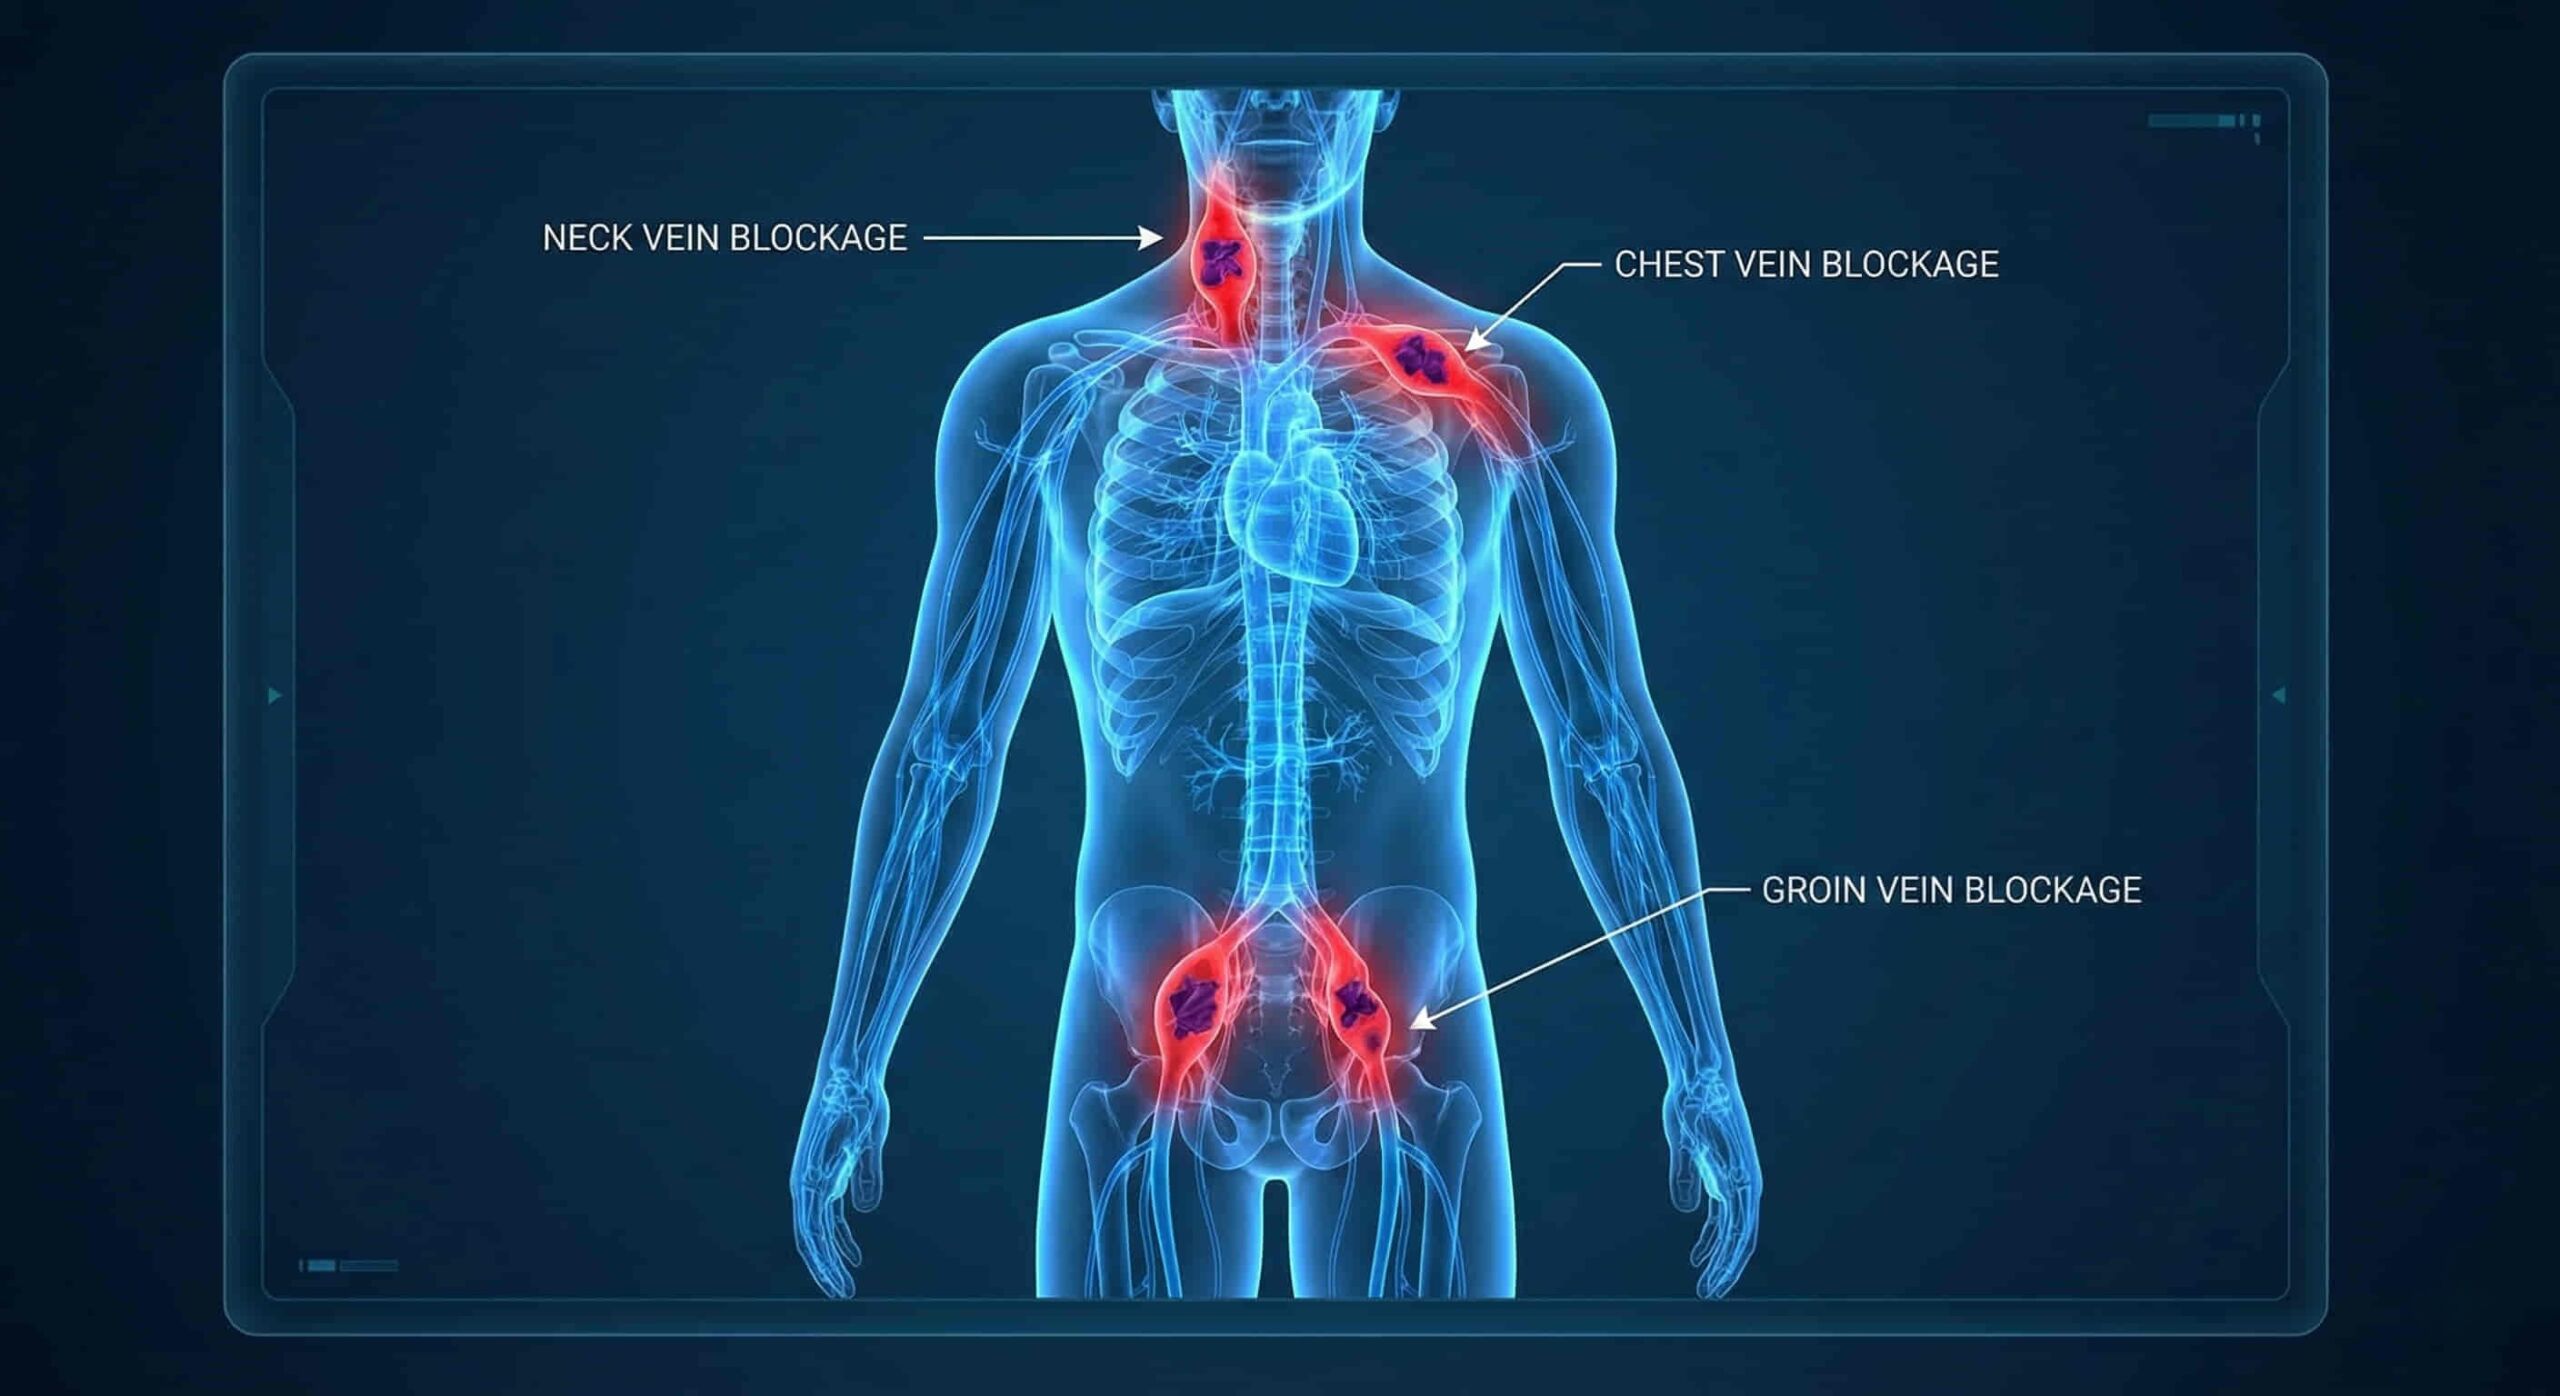

- For patients who depend on long-term dialysis or intravenous therapy, reliable central venous access isn’t optional—it’s life-sustaining. But repeated catheter use can close off the usual veins in the neck and chest, leaving patients with limited options.

- Exhausted Access: Patients who have no usable veins left in the upper body (neck, chest, or arms) due to multiple previous blockages.

- Failed Recanalization: When attempts to reopen blocked neck veins have not been successful.